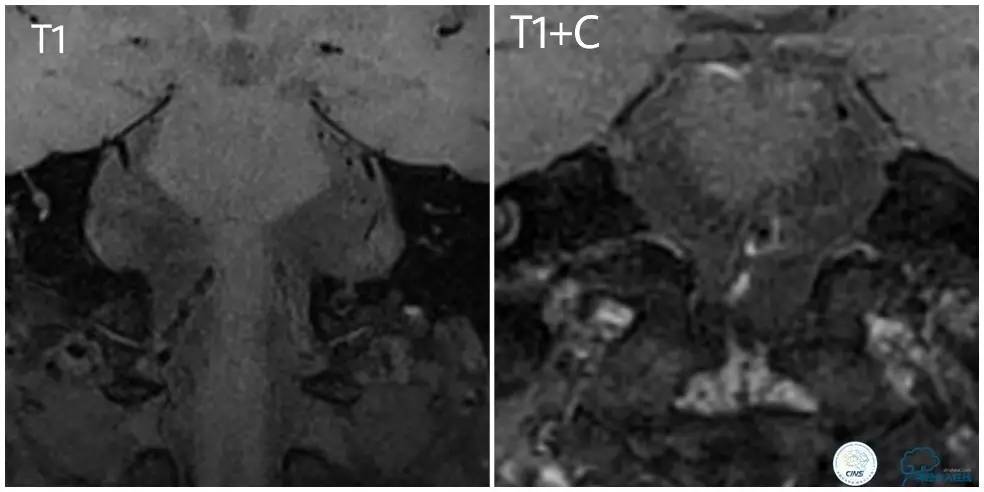

高分辨核磁(图4):右椎动脉颅内段右侧壁增厚,斑块形成,双侧椎动脉管腔狭窄,斑块形成。增强扫描示:双侧椎动脉及基底动脉可见不规则强化,右椎动脉及基底动脉为著。考虑右椎动脉颅内段右侧壁斑块形成,双侧椎动脉管腔狭窄、斑块形成,基底动脉管腔狭窄、管壁不规则增厚。

图4